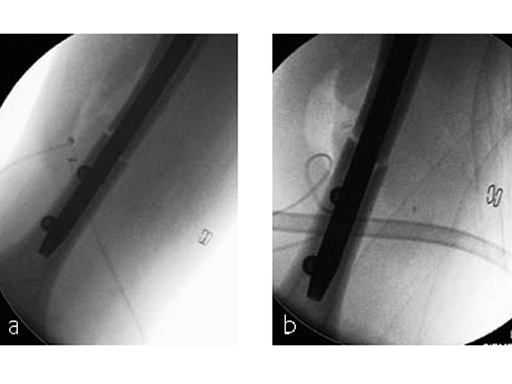

After neurosurgical intervention, surgery of the humerus was planned 10 days after the index trauma. The patient was still at the neurological intensive care unit and a preoperative clinical examination of the patient, regarding radial nerve palsy, was not possible. Therefore, a surgical revision with exploration of the radial nerve and an osteosythesis of the humerus using a long MultiLoc Humeral Nail was indicated.

The patient was operated on in beach chair position. For the exploration of the radial nerve, a limited anterolateral approach was used. The nerve was mobilized and retracted laterally. An anterolateral approach to the proximal humerus was performed. The supraspinatus showed a small acute rupture without retraction. The supraspinatus tendon was split to get access to the insertion area on the humeral head. A 270 mm long MultiLoc Humeral Nail of 8.5 mm diameter was inserted under visual and x-ray control to the desired endpoint. Reduction of both the proximal and the distal humerus fracture was anatomical. In the lateral view there was a small gap, and it was decided to apply compression after distal locking (Fig 12). Proximally, three MultiLoc screws were inserted and a 2 mm end cap was placed. Finally, the supraspinatus rupture was reconstructed with transosseous sutures and secured with an augmentation plate. The posterior greater tuberosity fracture was secured with Fiber Wire to the MultiLoc screws. Fig 13 illustrates the definitive fixation.

Postoperatively, no sling was used because the patient stayed in medically induced coma.